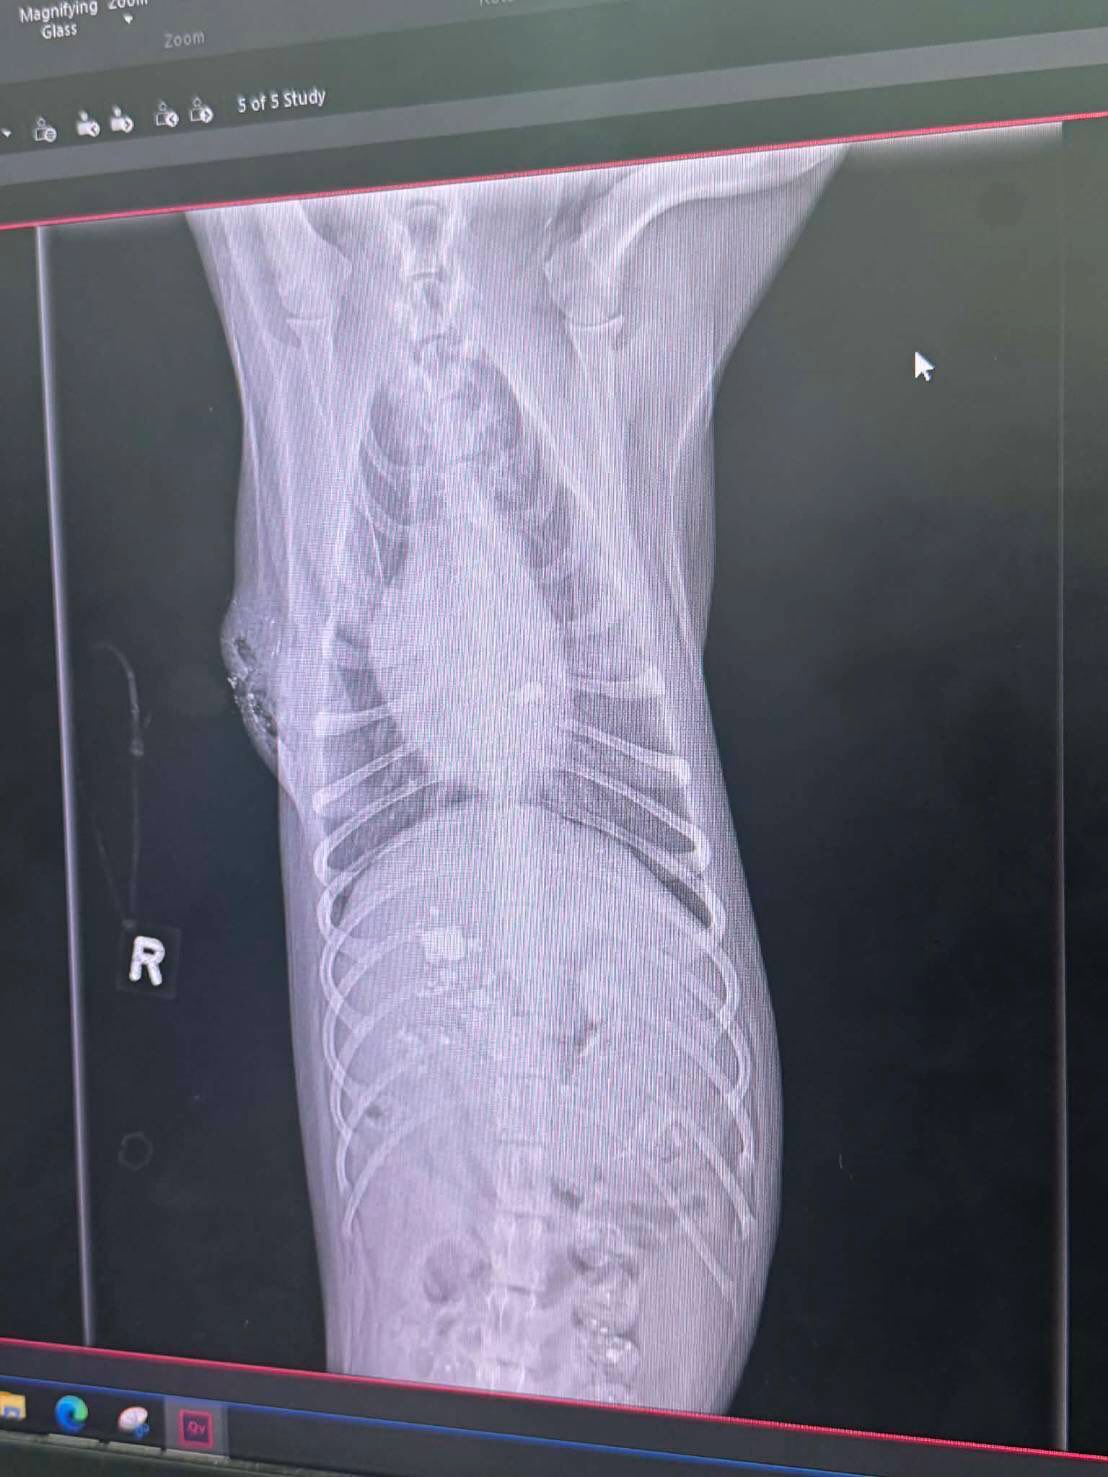

เนื่องจากมีสะเก็ดทะลุเข้าไปฝังข้างในตัวน้องบังเกอร์ บุ๋มเลยขอให้ทางทีมงานองค์กรทำดี ขับรถไปรับน้องจากโรงพยาบาลสัตว์ที่สุรินทร์ มาทำการรักษาต่อที่โรงพยาบาลสัตว์ทองหล่อในกรุงเทพฯ เพราะต้องใช้เครื่อง CT scan ตอนนี้น้องอยู่ในความดูแลของคุณหมอที่เรียบร้อยค่ะ ขอบคุณน้อง @kaechollada ที่ช่วยประสานงานให้นะคะ 🙏🏻🥰 ขอกำลังใจให้น้องบังเกอร์ด้วยครับ